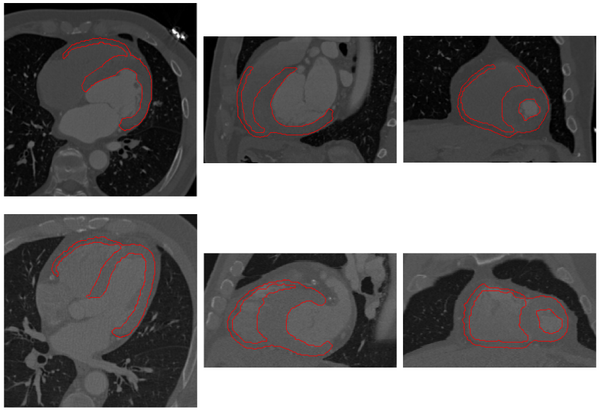

The proposed method has been tested using 30 human and 12 pig cardiac CT images. Examples of segmentation for human and pig data are shown below.

Myocardium segmentation results of human data with significantly different heart shapes.

Myocardium segmentation results of pig data with different volume coverages.